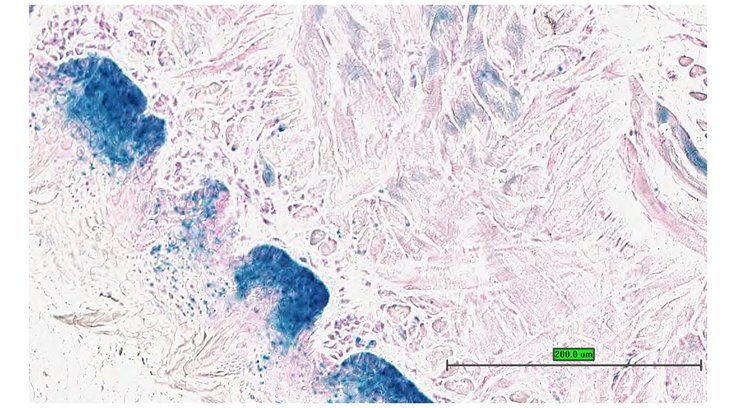

Specimen UC Davis_1873109: postnatal adult; Cox15tm1.1(KOMP)Vlcg/Cox15+ (more )

Structure Level Pattern Image Note

TS28: metanephros Present UC Davis_1873109 kidney

TS28: liver Present UC Davis_1873107

Specimen UC Davis_1873108: postnatal adult; Cox15tm1.1(KOMP)Vlcg/Cox15+ (more )

TS28: liver Present UC Davis_1873108